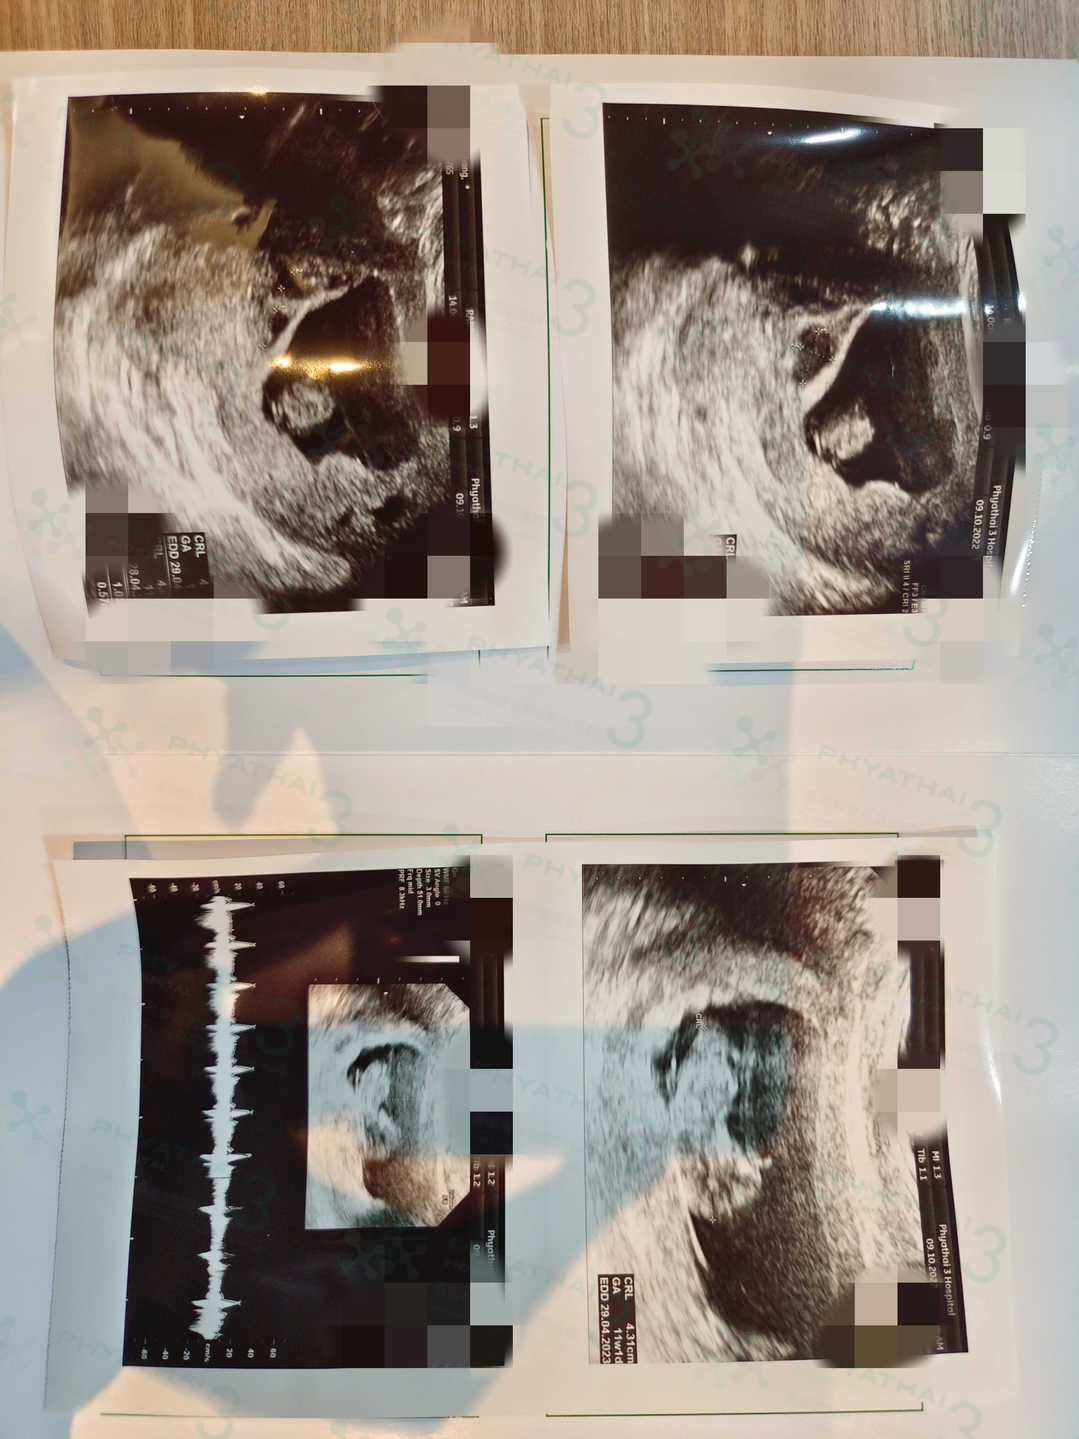

姐妹是在泰国疫情还是半开放时候来到的泰国,转眼间,在帕3试管的几个月就过去啦,时间过得很快。目前,泰国疫情已经完全放开,而姐妹也已经怀孕11周 ,快要回国啦,库医生通过超声检查看到宝宝按照孕期正常发育中也是感到特别开心。知道姐妹快要回国养胎后,库医生也是想着要在姐妹回国前把姐妹的身体调理得更好。现在准妈妈和宝宝都很好哟,姐妹终于可以带着宝宝回国啦。希望之后宝宝也要顺顺利利的出生长大哟~